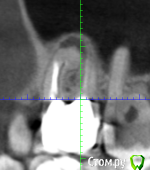

Техник глядя на снимок сказала что над шестерками гранулема (если я правильно запомнил термин). Корни торчат в пазухи.

По снимку стало ясно, что на шестерках не пролечено по каналу (как раз над тем где воспаление) а еще не пройден один до конца.

Выяснилось что те каналы, что пройдены - пройдены резорцин-формалином (если правильно запомнил название), то есть хрен распломбируешь.

Периодические воспаления носовой полости с левой(по направлению моего взгляда) стороны. Зуб шестерку я натурально чувствую, не как живой зуб, ничего не больно, а как будто что-то внутри зубной лунки почесывается/раздражено. С правой стороны такого нет, хотя похожая ситуация. По ощущениям обостряется когда ем сладкое, соответственно почти бросил. Нюх только с правой стороны остался. Когда воспаляется общее состояние угнетенное.

1) Картинки (не знаю тот ли кусок но воспаление вроде бы видно ) по возможности уменьшил размер, прикрепил к сообщению. Если нужно будет другие - подскажите, сделаю.